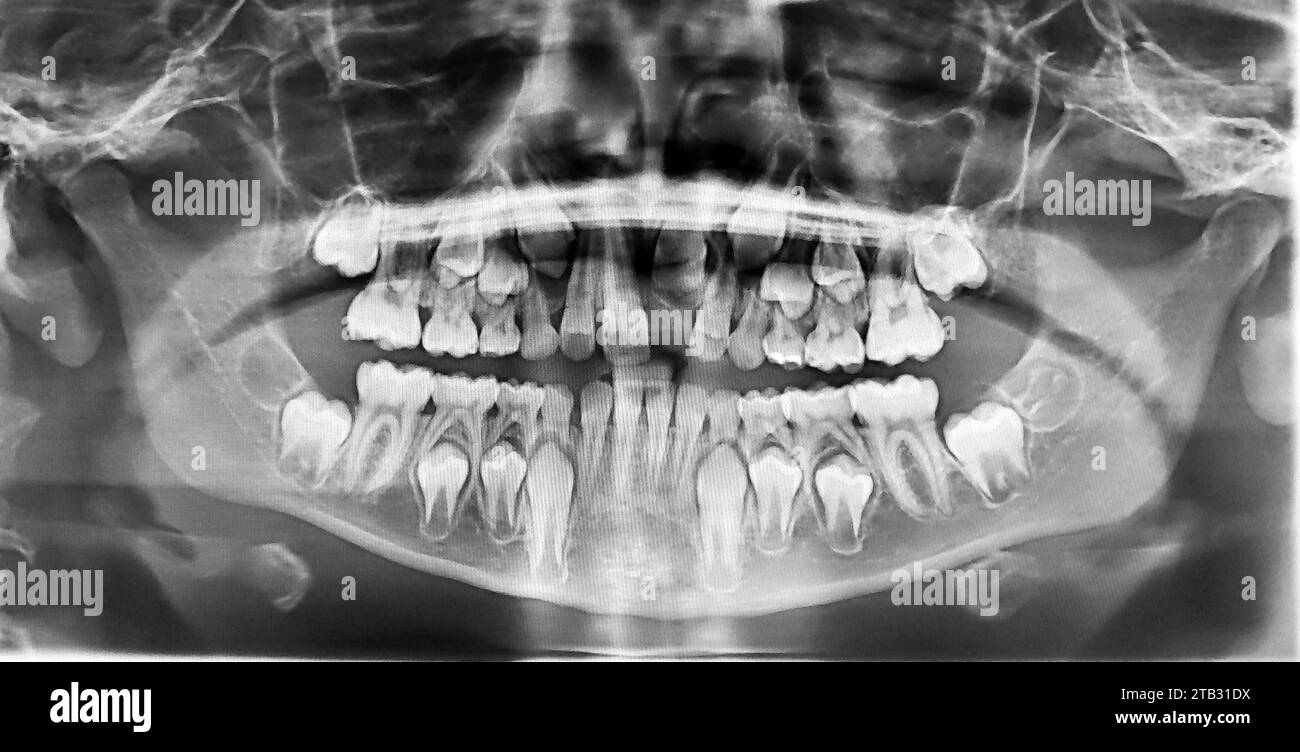

From www.alamy.com

Real capture of an xray of the teeth of a 10yearold child Stock How Many Teeth Does A 10 Year Old Have Shortly after age 4, the jaw and facial bones of the child begin to grow, creating spaces between. When a child gets to age 5 or 6, these. There are 10 on the upper jaw (top teeth) and 10 on the lower jaw (bottom teeth). In total, 20 baby teeth come through. Most kids have their first set of teeth. How Many Teeth Does A 10 Year Old Have.